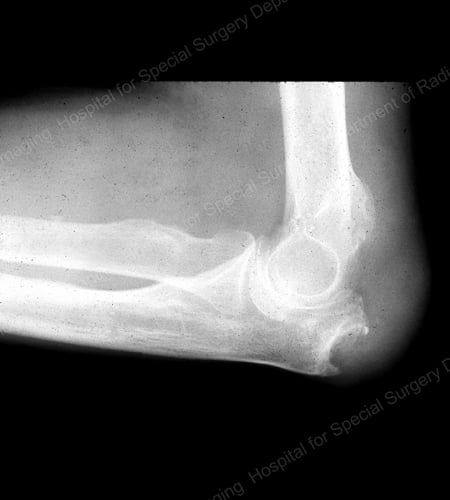

X-ray of gouty erosion at the proximal ulna at the elbow

Figure 16: Gouty Erosion at the Proximal Ulna at the Elbow